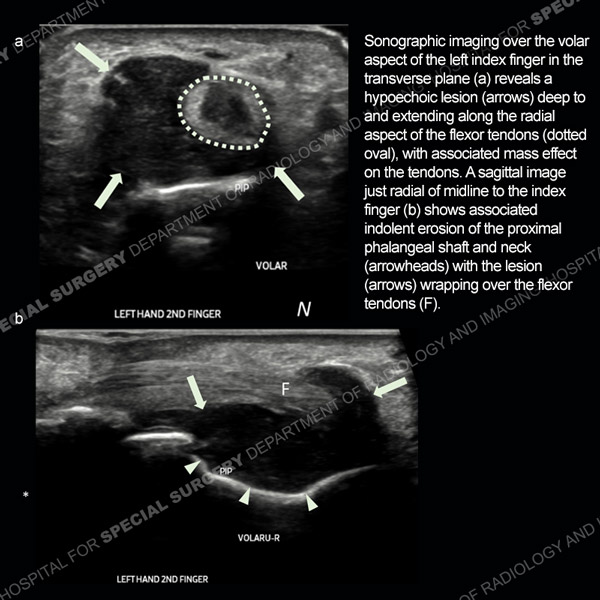

Featured Ultrasound of the Month CaseCase 186: 64-year-old woman with new left ring finger soft tissue swelling. |